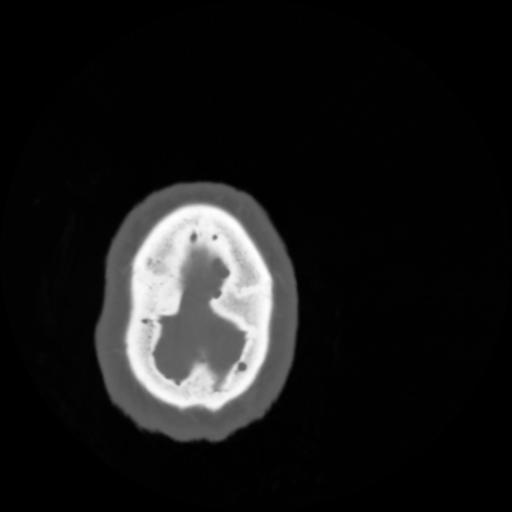

4 CEREBRO,,Vol,0.5,CEREBRO,,